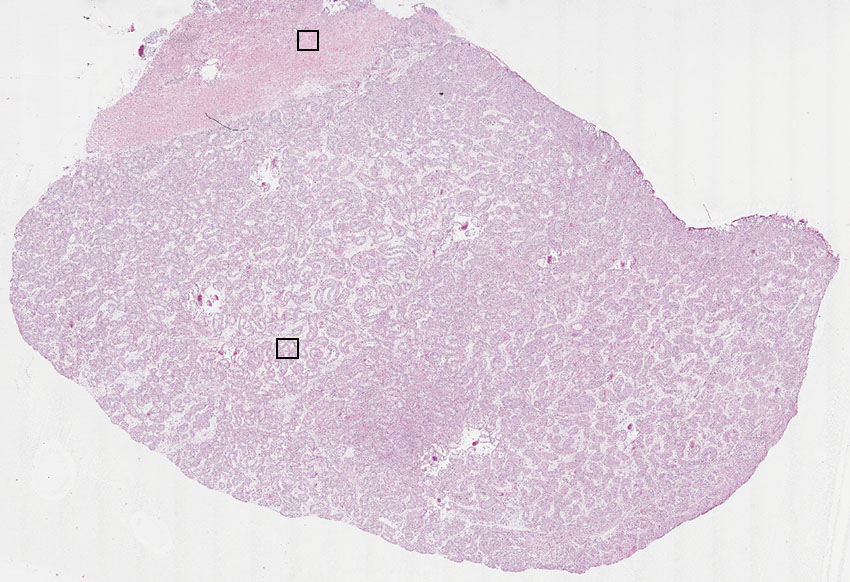

Cells in seminiferous ducts:

Other cell types: